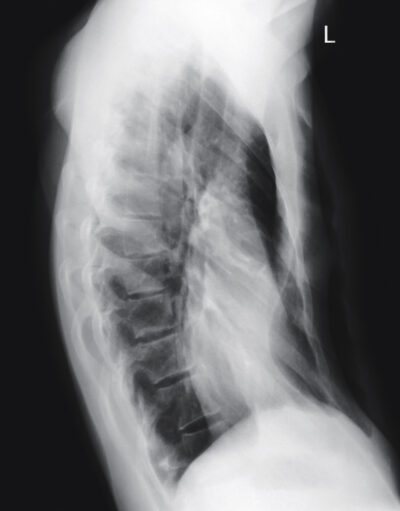

Pectus excavatum is a deformity of the chest in which the chest looks sunken or caved in. It occurs when the cartilage that holds the ribs to the breastbone has a defect and pushes the breastbone inward, leaving a deep dent in the centre of the chest between the pectoralis major muscles.

The cause of this chest deformity is unknown however it is more common among those with Down’s syndrome, Edwards syndrome, connective tissue disorders such as Marfan syndrome and those with homocystinuria or morquio.Pectus excavatum may be mild, moderate or severe and depending on each individual case, surgical repair may or may not be needed. For those who have more severe pectus excavatum the breastbone puts pressure on the heart and lungs, and the sunken chest creates issues with self-esteem and confidence, surgery may be needed to relieve the pressure and correct the deformity.